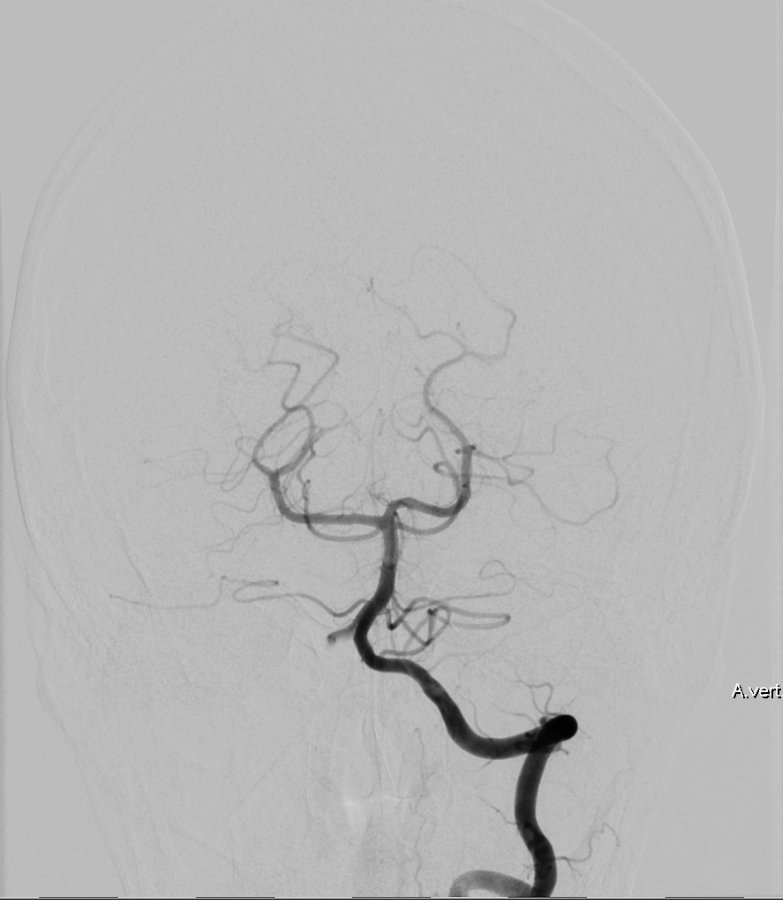

Bildgebung

Der Goldstandard zur optimalen Darstellung der Arteria vertebralis ist die digitale Subtraktionsangiographie, kann jedoch je nach klinischer Fragestellung auch in der CT-Angiographie oder MRT Bildgebung dargestellt wird.

Aneurysmen

Im Bereich der Arteria vertebralis können typischerweise Dissektionsaneurysmen auftreten und eine Subarachnoidalblutung verursachen[^3]. Die Behandlung dieser Dissektionsaneurysmen kann je nach Fall beispielsweise endovaskuläre mithilfe von Implantation eines Flow-Diverters behandelt werden[^4] [^5].